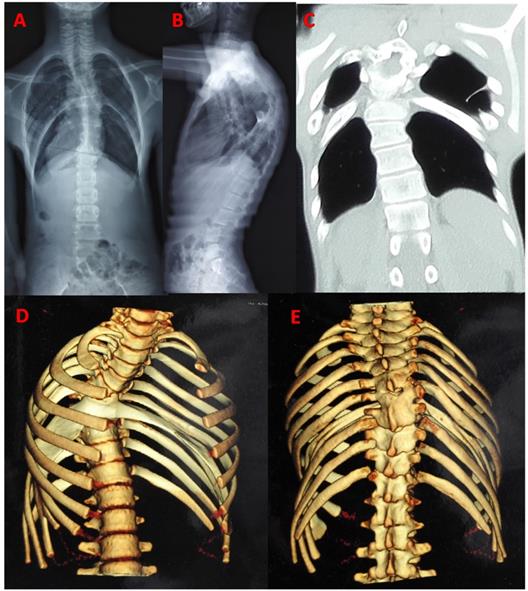

In all cases, the majority were demonstrated by plain film, conventional tomography or three dimensional CT. Three cases were confirmed by surgery, and other three were found by autopsy. In the past, three patients have been subjected to unnecessary thoracotomy. Expansion of the rib head, tent-like pleural extension and intrathoracic fat were identified to special imaging features in previous studies [33,57] (Fig. 3). These features were very helpful for correct diagnosis of intrathoracic rib on the era of only X-ray. But now it is more easily using CT scan and three dimensional reconstructions.

Figure 3

Typical image: a 13-year-old man with bilateral bifid intrathoracic rib. postero-anterior and lateral radiograph showed kyphoscoliosis in thoracic spine, and four thoracic cavity compartments were separated by bilateral intrathoracic rib (A, B). The coronal CT showed two deformed rib extending inferolaterally in bilateral hemithorax, forming focal additional compartment with fiber band-like attachment to pleura (C). CT scan with 3D reconstruction showed bifurcated rib articulated with anterior aspect of the T5 vertebra. Distal anomalous rib had osseous connection with adjacent fused rib, extending bifid rib locally depressed into the thoracic cavity (D, E).

On some occasions, intrathoracic ribs exhibit diaphragmatic attachments, usually in the form of a fibrotic band or fat layer. In all cases, 18 (26.5%, 18/68) were attached to diaphragm and 50 were no diaphragmatic attachment. Four of the cases (5.9%, 4/68) had fiber band attachment to the pleura with tent-like pleural extension. Only one case had fibrous band attaching to the T9 right side with thoracic scoliosis [43]. Six cases (8.8%, 6/68) had mild thoracic scoliosis and two with bloc vertebra. One case had congenital thoracic kyphoscoliosis [58]. Only one case had reported incidental associated findings include right-sided aortic arch [8] and liver eventration [41]. Two cases had an additional rib anomaly, bilateral hypoplasia 1st rib and cervical rib [9,22].